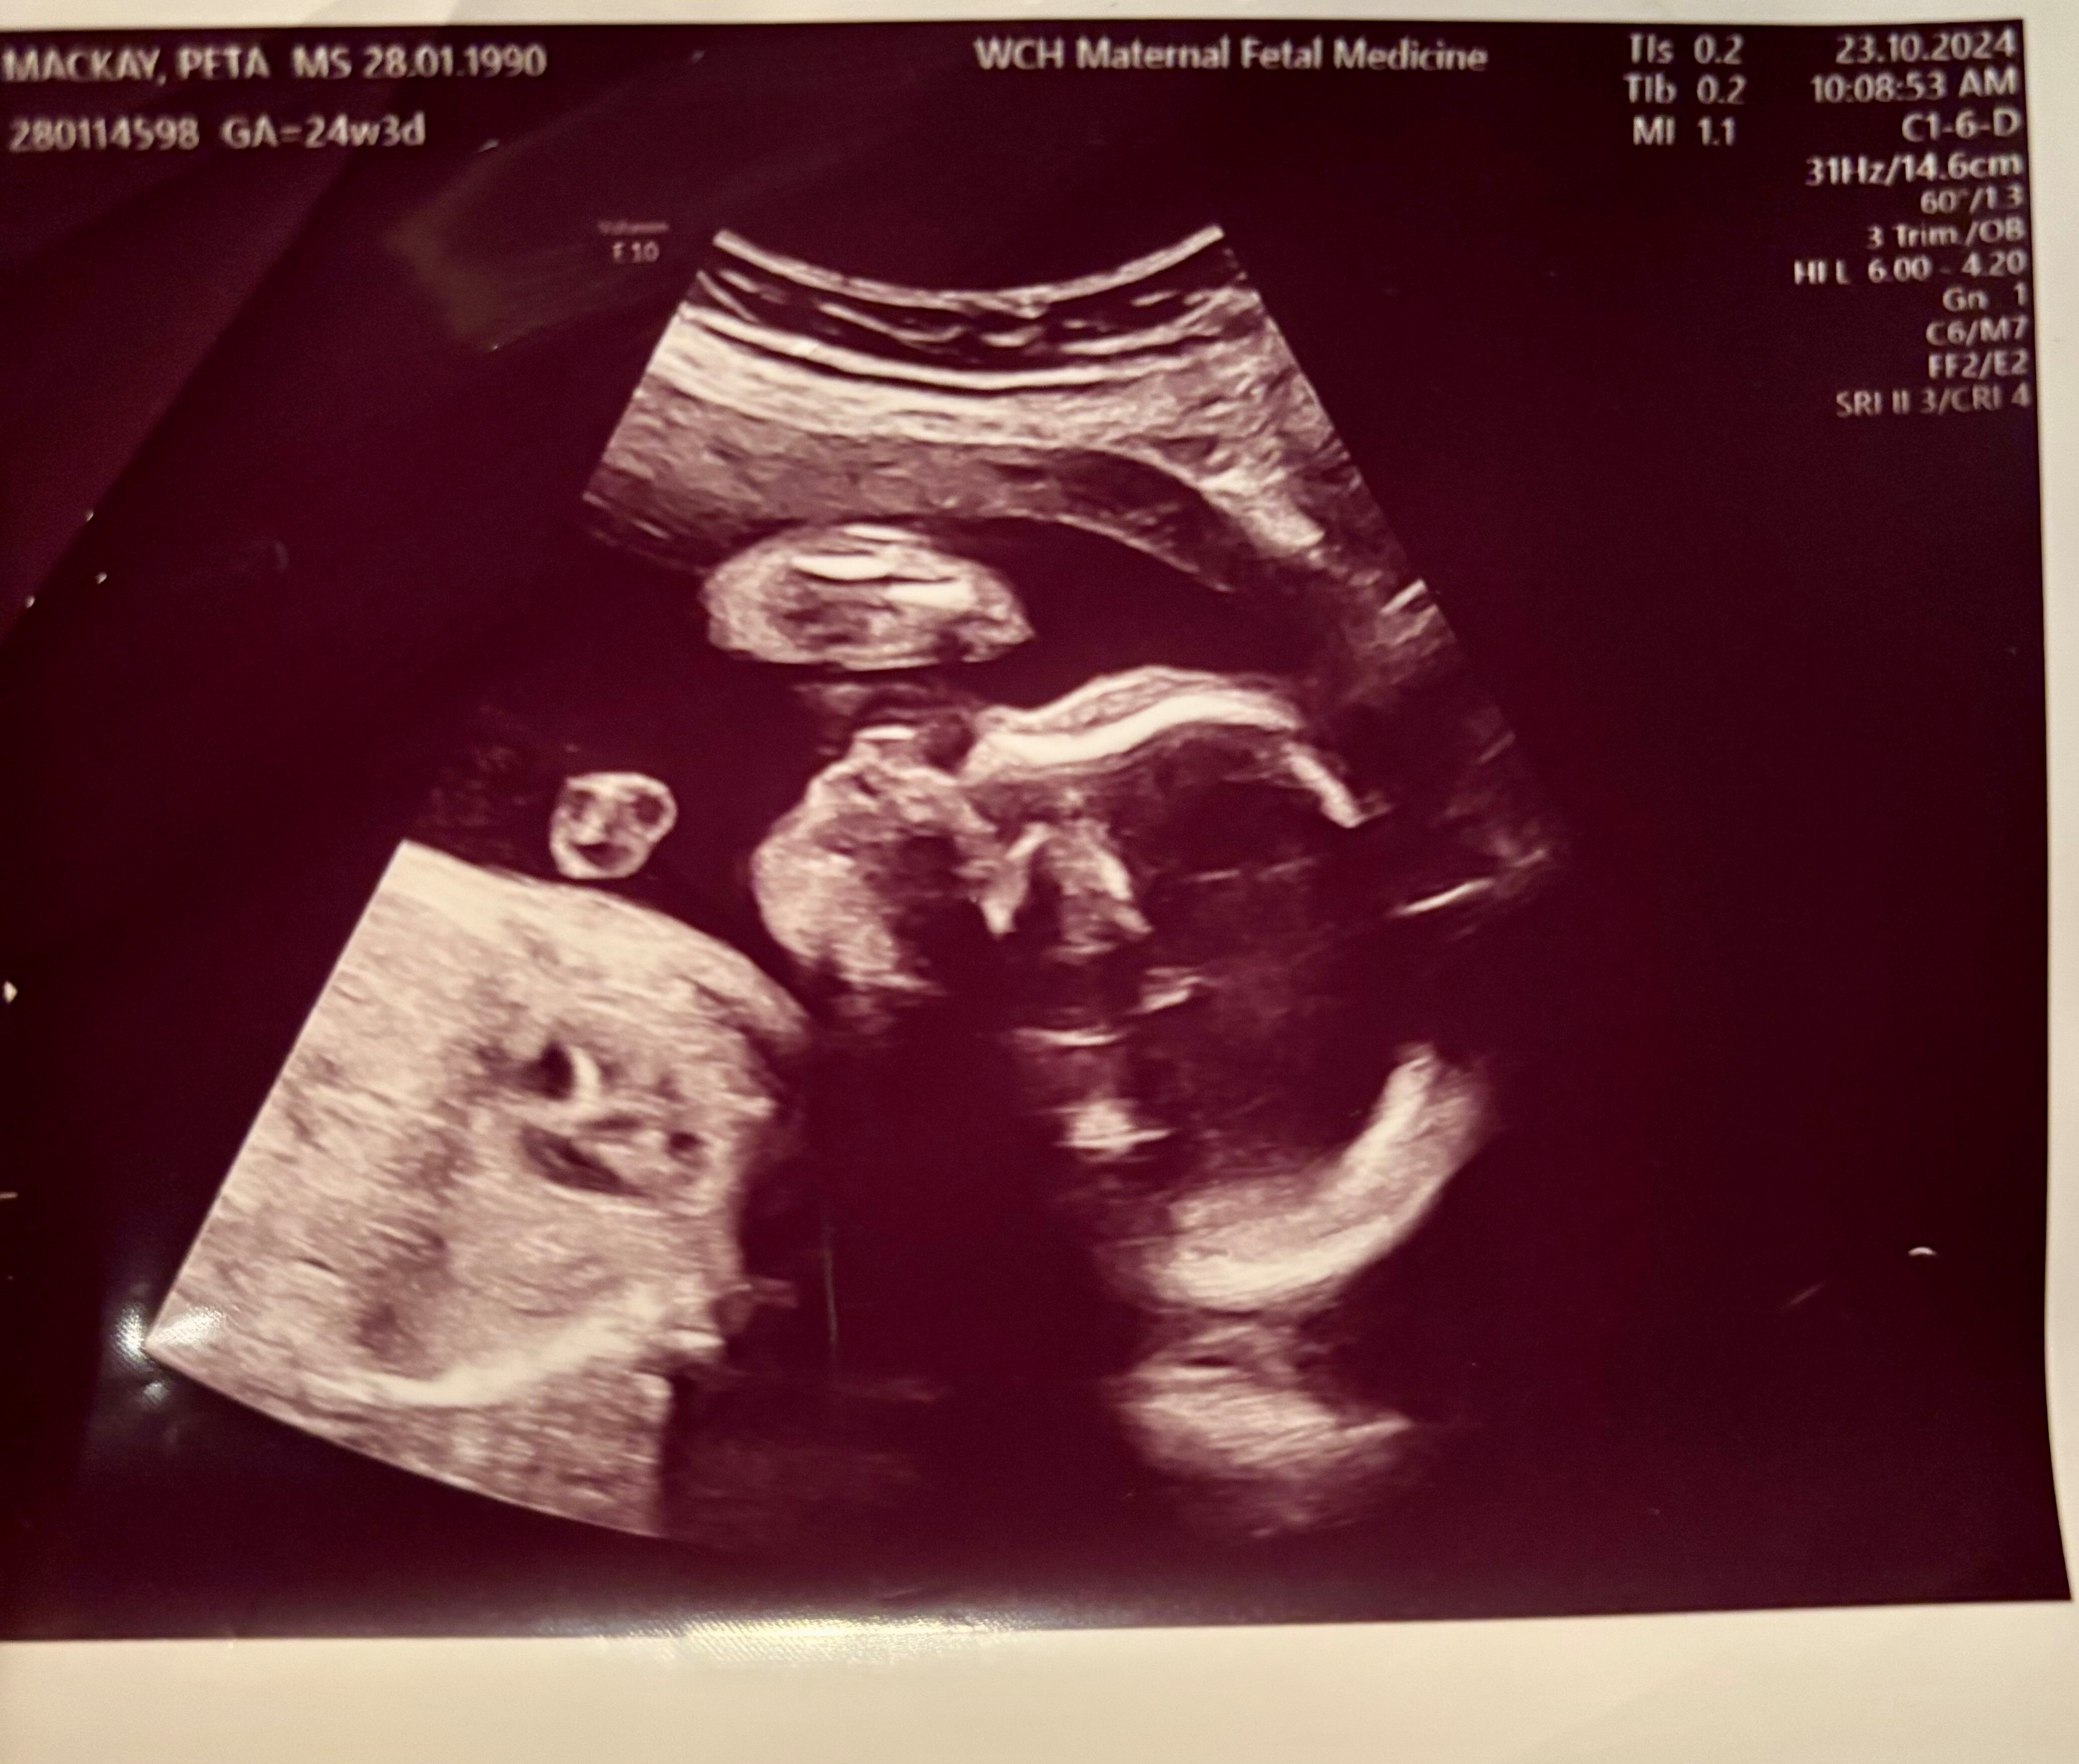

After three years of trying for a baby, Peta's pregnancy came as a surprise just after they picked up their first IVF kit. However, complications arose during a routine 20-week ultrasound, revealing a cyst on the fetus's lung, leading to a diagnosis of congenital cystic adenomatoid malformation (CCAM).

A routine ultrasound at 20 weeks showed cysts on the fetus's lungs.

This condition classified her pregnancy as high-risk, necessitating fortnightly check-ups in Adelaide, nearly 1,000km from home.